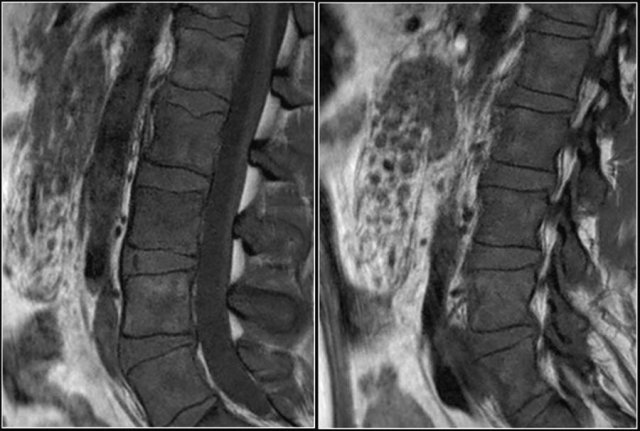

Here a patient with multiple osseus metastases.

At the level of L1L2 this causes spinal stenosis with compression of the nerves (red arrow).

It is not that common for metastases to cause nerve compression at the lumbar level.

At the thoracic and cervical level metastases frequently cause compression because there is not much CSF surrounding the myelum.